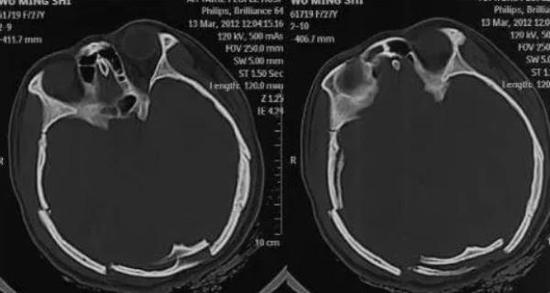

根據《網易》報導,大陸安徽一名女高中生2012年3月11日晚自習結束後獨自走回家,卻在路上被人拖到草叢性侵,凶手還重擊她的頭顱,相當凶殘,造成她顱骨多處粉碎性骨折和顱內出血,不僅意識模糊、呼吸不暢、大小便失禁,還因為枕葉受損造成雙眼失明

▼女學生做頭部電腦斷層攝影檢查。(圖/翻攝自《網易》)